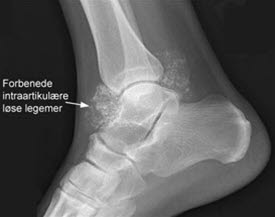

Røntgenbilde vil et stykke ut i forløpet som regel gi diagnosen og viser mange forkalkede biter inne i leddet. Det kan også foreligge slitasjeforandringer. Tidlig i sykdomsforløpet kan det mangle forkalkninger. MR er den beste undersøkelsen og kan være nødvendig ved manglende funn ved andre undersøkelser eller før en eventuell operasjon.